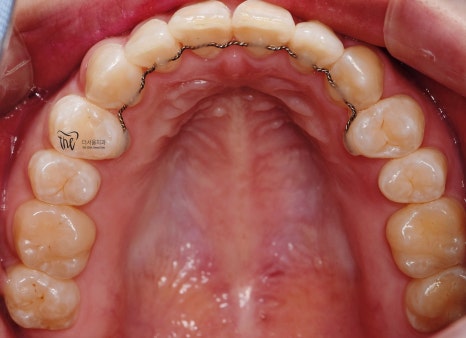

『인비절라인 치료 진행』

그리고, 저희 병원에서의 특기죠.

인비절라인.

투명장치로 치료를 받기로 했고,

저와 호흡을 맞춰서 후딱후딱

정밀진단부터 시작을 했으며

어태치먼트들 부터 부착을 해나갔습니다.

치아의 면에, 뾰족뾰족 튀어나온 것들이

바로 어태치먼트들입니다.

이게, 투명 템플릿과 만나서 올바른 치열의

형태로 탈바꿈 될 수 있도록 돕는 핵심 역할을

합니다.